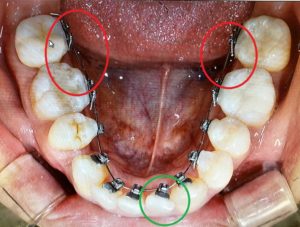

今回は口蓋につけたインプラントの役目になります。

通常、矯正の場合ワイヤーでつながれた歯はお互いを引っ張り合います。

したの画像で言うと、抜歯した4番の穴を境目にして前歯側と奥歯側は引っ張りあうことになります。

前歯も奥歯も動くので抜歯したすき間を前歯の矯正のために有効活用できない可能性が出てきます。

矯正用のインプラントを利用すると・・・

赤○内のインプラントから両側の奥から2番目を結束して固定(※画像では青い直線でつないだイメージにしています)すると、奥歯が前方向に動くことを抑制します。

アンカーインプラントのアンカーとは碇のことです。

インプラントが碇の役目をして動こうとする歯をとどめます。

そして、前歯側が後ろに下げられるスピードが速くなります。

私の場合、抜歯のすき間がふさがるスピードが速くなるのとあわせて、前歯のガタガタもなおり、綺麗なアーチ型ができるスピードが上がります。

<矯正インプラント装着時 2018/11/03>

※わずかずつですが、前歯のアーチが形成されつつあります。